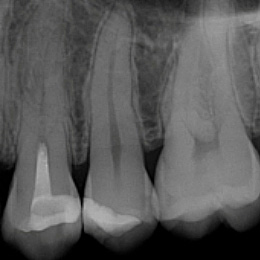

Fallbeispiel: Revision 46 (und 45) Recall 6 Monate

Bringt eine Wurzelkanalbehandlung nicht den gewünschten Erfolg, bedeutet dies nicht, dass ein Zahn nicht mehr zu erhalten ist. Mit einer Revisionsbehandlung können auch bereits wurzelkanalbehandelte Zähne langfristig erhalten werden!